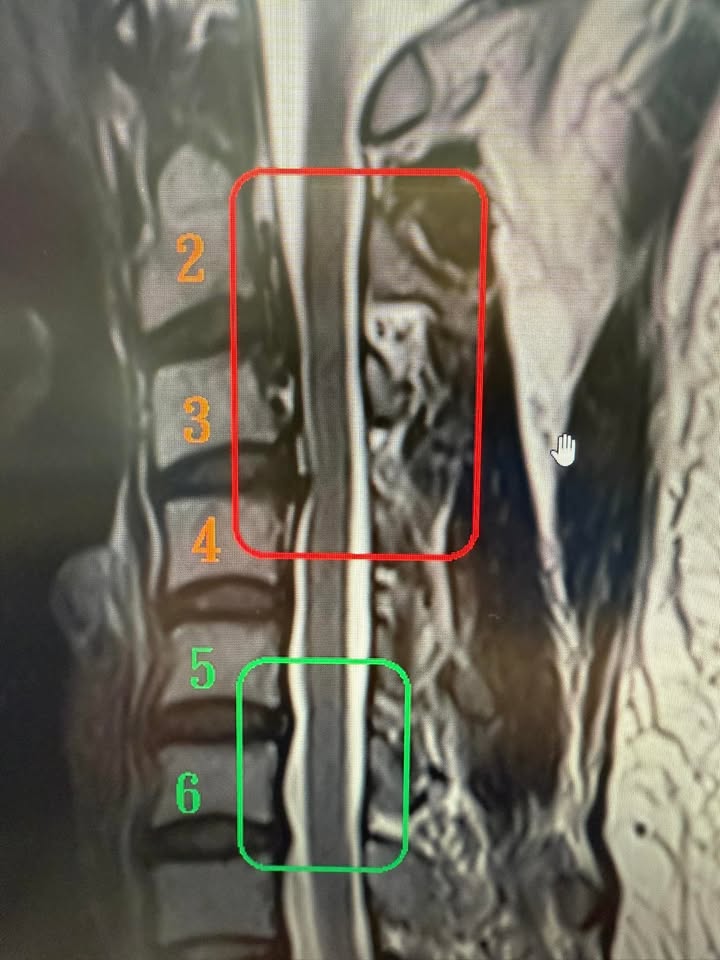

Cervical Spine Treatment Cases 精彩回顧 患者高爾夫球影片親自見證 2025.01.17 椎管狹窄曾經很難很難的病也有一線曙光 2025.01.19 2025.01.20 27歲陳小姐的巨大椎間盤突出康復之路 2025.01.23 2025.01.30 嚴重腰椎滑脫與椎管狹窄的重生之路 2025.02.05 嚴重心悸伴隨視力模糊跟血壓飆升 2025.02.07 頸椎脊髓壓迫導致手麻跛行掰咖 2025.02.11 椎間盤突出合併椎管狹窄的奇蹟之旅 2025.02.12 巨大椎間盤突出治療醫案 2025.02.13 擺脫腰痛束縛原來是椎間盤突出 2025.02.18 L小姐的交感神經症候群從痛苦折磨到重生 2025.02.19 半年無法站立原來是椎間盤巨大突出 2025.02.21 2025.02.23 2025.02.25 ← 上一頁 28 29 30 31 下一頁 →